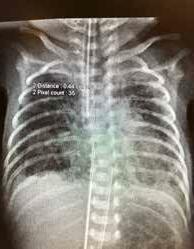

Fysiologi og hemodynamikk I de første minuttene etter fødselen skjer det store fysiologiske endringer i barnets respirasjon og sirkulasjon. Lungene tar over som gassutvekslingsorgan, og den vaskulære mostanden i lungearteriene synker som følge av økt oksygenkonsentrasjon. Når lungekarmotstanden faller, fylles lungene med blod som deretter strømmer via lungevenene tilbake til venstre hjerte halvdel (Fig.1). Dette sikrer god fylning (preload) til venstre ventrikkel som kan opprettholde et tilstrekkelig slagvolum. Slik unngår barnet store blodtrykksendringer (1, 2)

Dersom barnets lunger ikke fylles med luft, forblir lungekar motstanden høy, og det går lite blod til lungene. Avklemming av navlesnoren i denne situasjonen vil kutte blodforsyningen til barnet via navlevenen, og venstre ventrikkel får redusert fylning (preload), fordi manglende venøs retur fra placenta ikke kompenseres av økt venøs retur fra lungevenene. I tillegg øker motstanden i systemkretsløpet (afterload) på grunn av at navlearteriene er avklemt. Dette kan føre til kardiovaskulær instabilitet i de første, viktige minuttene av barnets liv og forstyrre transisjonsprosessen.

Intakt navlesnor inntil barnet har etablert pulmonal gassutveksling, gir mer stabil hemodynamikk med potensielt store gevinster, blant annet redusert risiko for hjerneblødning. Så lenge navlesnoren er intakt, kan noe gassutveksling fortsatt foregå gjennom placenta og beskytte mot asfyksi, selv om barnet er utenfor uterus.

Figuren viser mekanismer for ustabil hemodynamikk ved tidlig avnavling. Modifisert fra referanse 2, Uwins et al, med tillatelse.